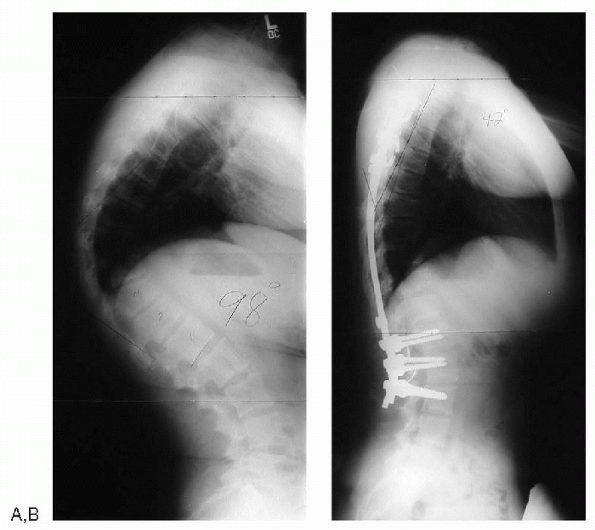

Figure 7.5-6 (A) Standing lateral radiograph of a patient with Scheuermann’s disease. (B) After anterior releases and posterior spinal fusion with instrumentation.

|

from postural kyphosis (Fig. 7.5-6).

can be weaned with the onset of skeletal maturity. Surgical treatment

is reserved for patients with severe deformity (more than 75 degrees)

and those with neurologic compromise. Surgical options include

posterior spinal fusion with instrumentation and combined anterior

release with posterior fusion with instrumentation. The posterior-only

approach is generally reserved for skeletally immature patients or

skeletally mature patients with a kyphosis that corrects to at least 50

degrees on hyperextension lateral views. The anterior approach may be

performed either open or thoracoscopically. Overcorrection should be

avoided. Complications include the development of a junctional

deformity either above or below the fusion and neurologic compromise.